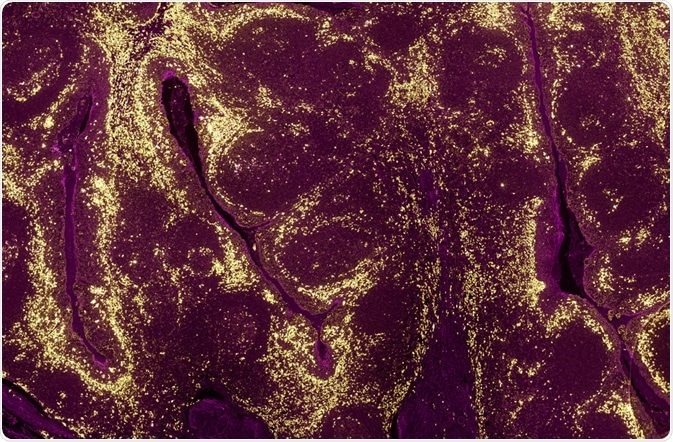

A tumour sample where the levels of different proteins in cell populations have been identified using a fluorescently labelled antibody and fluorescence microscopy. (Carl Dupont | Shutterstock)

Apart from signaling, structure, and function, the fluorescence of a protein can also be used to measure the levels of a protein expressed inside a cell or a tissue. This can be used in cases where the fluorescent probe is recombined with the gene or reporter of a gene. The expression of the reporter, in this case, reflects the levels of protein it is recombined with.